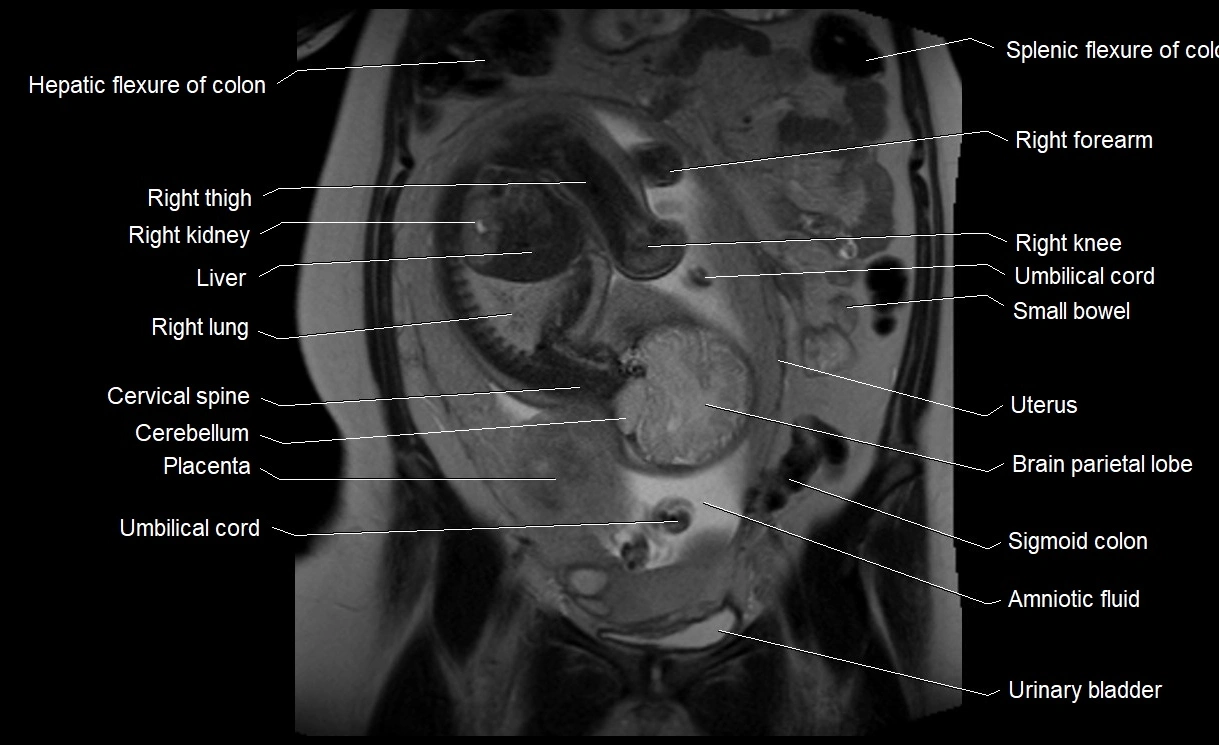

Amniotic fluid is the protective liquid surrounding the fetus within the amniotic sac. It plays an essential role in cushioning the fetus, enabling fetal movement, maintaining temperature stability, and allowing for normal lung and musculoskeletal development.

Relations

• Enclosed within the amniotic sac, bounded by the amnion and chorion

• Surrounds and cushions the developing fetus

• In continuity with maternal circulation through placental and transmembrane exchanges

• Imaging relevance: MRI used for fetal visualization and assessing oligohydramnios/polyhydramnios when ultrasound is inconclusive